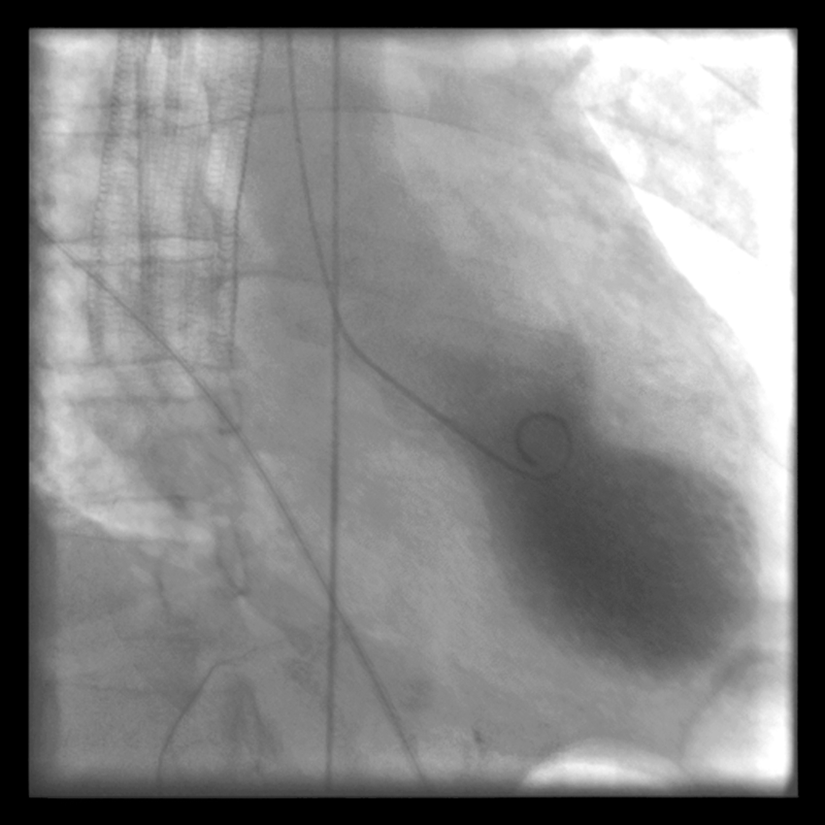

Hastalar hastaneye baş vurduklarında görülen belirtiler ilk olarak kalp krizini akla getirir. Bu hastaların kan değerleri, EKG ve anjiyografi sonuçlarına göre tanı konulabilir.

Takotsubo kardiyomiyopatisi sırasında kalpte oluşan balonlaşma, Japon balıkçıların ahtapot yakalamak için kullandığı kaba benzer form aldığı için bu ad verilmiştir. Aslında isim açısından zengin sayılır. Halk arasında "kırık kalp sendromu", "stres kardiyomiyopatisi", "ampulla kardiyomiyopatisi", "geçici sol ventrikül apikal balon sendromu" gibi isimlerle bilinir.